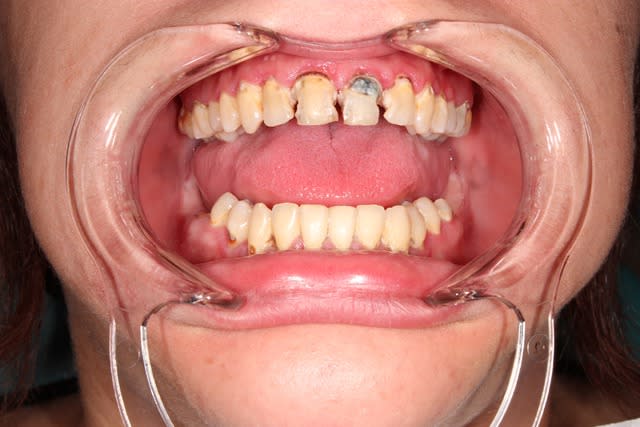

Comme celle ci : 21 ans.

Je parie qu'elle venait pour un blanchiment ^^

Presque.

Elle venait pour refaire ses deux centrales et parraissait trés motivée.

Il y avait un paquet de caries un peu partout aussi.

J'ai réussi à lui faire utiliser la brosse a dents avec un résultat encourageant dés le deuxième rendez vous.

Du coup je me suis lancé dans 2 endos. Elle n'est jamais revenue ensuite. Peut etre que ses deux centrales se sont couronnées toutes seules. Du moins c'est la seule explication que j'ai trouvé.

Mais je n'ai rien perdu, car je me sers de sa photo pour expliquer aux jeunes ado l'utilité du brossage. La question qui tue : "embrasserais-tu cette fille ?"